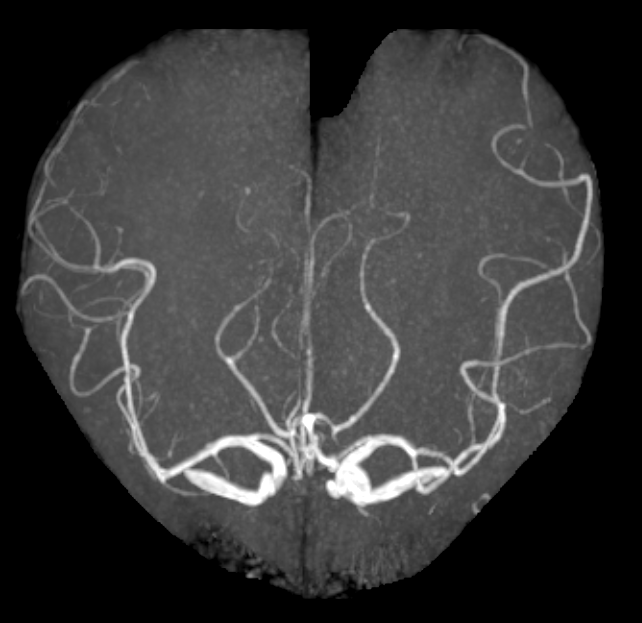

术前MRA见左侧颈内动脉瘤: